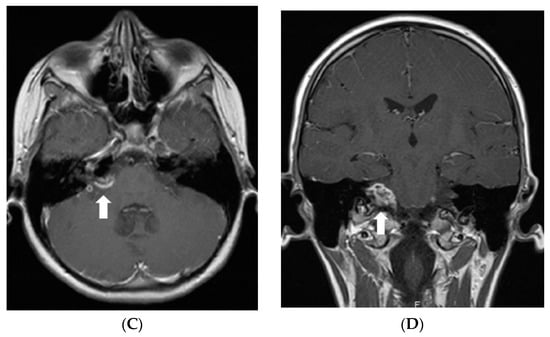

Five months after the first MRI, another MRI was performed, and it showed a new small enhancing nodule in the prepontine cistern at the pontomedullary junction, in the expected location of the left abducens nerve (Figure 2).

Figure 2.

Follow-up MRI of the brain after the surgery (in December 2011). Axial post-contrast T1W image demonstrates a new enhancing nodule in the expected location of the cisternal segment of the left abducens nerve.